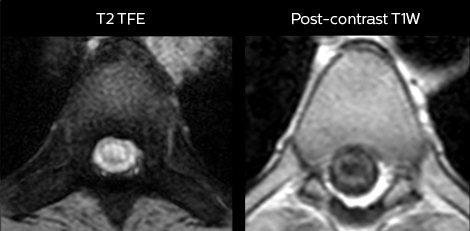

in image acquisition and postprocessing algorithms.”“mDIXON TSE sequences allow simultaneous characterization of morphological changes from the in-phase T2-weighted images and visualization of edematous changes, thanks to the water T2-weighted images from the same acquisition. Anatomical and morphological considerations could be a partial or complete ligament tear, a bony avulsion or hematoma.” “For soft tissue assessment mDIXON brings similar benefits. For example in one T2-weighted mDIXON TSE acquisition, having the multiple contrasts helps us assess abnormalities in peripheral nerves fascicles, which may be due to anatomical or inflammatory changes..” “In peripheral joints, we get good image quality in difficult areas with mDIXON TSE. Fat suppressed images appear homogeneous over the entire image, even with large coverage at 3.0T – for instance in scapular or hip girdles – or in the bearing areas or around metal prostheses*, where fat suppression is often deficient with STIR or spectral fat suppression, causing diagnostic difficulties. If a diagnostic image is right the first time, we don’t need to repeat or add a sequence.” “mDIXON TSE sequences allow simultaneous characterization of morphological changes from the in-phase T2-weighted images and visualization of edematous changes, thanks to the water T2-weighted images from the same acquisition. Anatomical and morphological considerations could be a partial or complete ligament tear, a bony avulsion or hematoma.” “For soft tissue assessment mDIXON brings similar benefits. For example in one T2-weighted mDIXON TSE acquisition, having the multiple contrasts helps us assess abnormalities in peripheral nerves fascicles, which may be due to anatomical or inflammatory changes..”

“For soft tissue assessment mDIXON brings similar benefits. For example in one T2-weighted mDIXON TSE acquisition, having the multiple contrasts helps us assess abnormalities in peripheral nerves fascicles, which may be due to anatomical or inflammatory changes..” “In peripheral joints, we get good image quality in difficult areas with mDIXON TSE. Fat suppressed images appear homogeneous over the entire image, even with large coverage at 3.0T – for instance in scapular or hip girdles – or in the bearing areas or around metal prostheses*, where fat suppression is often deficient with STIR or spectral fat suppression, causing diagnostic difficulties. If a diagnostic image is right the first time, we don’t need to repeat or add a sequence.” “mDIXON TSE sequences allow simultaneous characterization of morphological changes from the in-phase T2-weighted images and visualization of edematous changes, thanks to the water T2-weighted images from the same acquisition. Anatomical and morphological considerations could be a partial or complete ligament tear, a bony avulsion or hematoma.” “For soft tissue assessment mDIXON brings similar benefits. For example in one T2-weighted mDIXON TSE acquisition, having the multiple contrasts helps us assess abnormalities in peripheral nerves fascicles, which may be due to anatomical or inflammatory changes..”